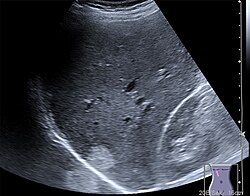

Die Sonografie ist das wichtigste Verfahren bei der Differentialdiagnose eines akuten Abdomens, bei Gallensteinen oder bei der Beurteilung von Gefäßen und deren Durchlässigkeit, vor allem an den Beinen. Weiterhin wird sie standardmäßig zur Untersuchung der Schilddrüse, des Herzens – dann Echokardiografie oder Ultraschallkardiografie (UKG) genannt –, der Nieren, der Harnwege und der Harnblase benutzt. Durch den Einsatz von Echokontrastverstärkern (Kontrastmittel) ist in geeigneten Fällen eine weitere Verbesserung der Diagnostik möglich.

Die Sonde sendet kurze, gerichtete Schallwellenimpulse aus, die an Gewebe-Grenzschichten und in inhomogenen Geweben unterschiedlich stark reflektiert und gestreut werden, was als Echogenität bezeichnet wird. Aus der Laufzeit der reflektierten Signale kann die Tiefe der reflektierenden Struktur ermittelt werden. Die Stärke der Reflexion wird vom Ultraschallgerät als Grauwert auf einem Monitor dargestellt. Strukturen geringer Echogenität werden dunkel bzw. schwarz, Strukturen hoher Echogenität werden hell oder weiß dargestellt. Gering echogen sind vor allem Flüssigkeiten wie Harnblaseninhalt und Blut. Eine hohe Echogenität besitzen Knochen, Gase und sonstige stark schallreflektierende Material-Grenzflächen. Die Echogenität innerhalb eines Organs oder eines Krankheitsherdes wird als Binnenecho bezeichnet.